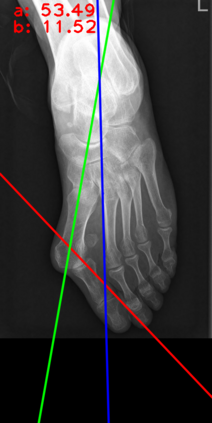

Angular measurements is essential to make a resonable treatment for Hallux valgus (HV), a common forefoot deformity. However, it still depends on manual labeling and measurement, which is time-consuming and sometimes unreliable. Automating this process is a thing of concern. However, it lack of dataset and the keypoints based method which made a great success in pose estimation is not suitable for this field.To solve the problems, we made a dataset and developed an algorithm based on deep learning and linear regression. It shows great fitting ability to the ground truth.